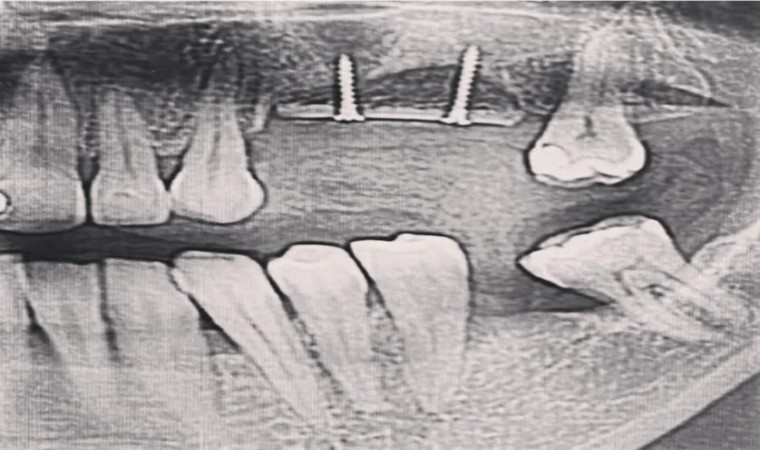

Diş Hekimi Özbaylar, üst çenelerde, dişlerin hemen üstünde bulunan anatomik boşluklara maksiller sinüs adı verildiğini ifade ederek, şöyle konuştu “Maksiller sinüsler hayat boyu büyümelerini sürdürürler. Sinüslerin hacmindeki artış, üst çenelerdeki kemik hacminde azalmaya yol açar. Fizyolojik olarak kabul edilebilecek bu kemik kayıpları, implant uygulamalarına olanak tanımayacak boyutlara ulaşabilir.Bu durumda, eğer implant terapisi uygulanacaksa, Sinüs Lifting adı verilen, özel operasyonlarla sinüslerin hacmini azaltıp, kemik hacmini artırmaya yönelik özel bir cerrahi müdahale uygulanmalıdır. Hastanın isteğine göre lokal ya da genel anestezi altında uygulanabilen bu operasyon ile çene kemiği ile sinüs mukozası arasına kemik partikülleri yerleştirilir ve takip eden altı aylık sürede kemik oluşumu beklenir. Bu amaçla hastanın kendi vücudundan alınacak kemikler kullanılacağı gibi, kemik bankalarından elde edilecek kemik ile inorganik yada organik materyaller de kullanılabilir.”

Kemik oluşumu tamamlandıktan sonra ise rutin implant uygulamalarına geçildiğini vurgulayan Özbaylar, sözlerine şöyle devam etti, “Ogmentasyon üst çene yada alt çenede Alveol Kemiği Ogmentasyonu (Genişletme) Diş çekimlerinden sonra, uzun dönemde karşılaşılan en büyük problemlerden biri çene kemiklerinde görülen erimedir. Diş kayıplarının tedavisi, implant uygulamaları ile giderilecekse kemik yüksekliği ve hacmi daha da önem kazanır. Implant uygulaması, belirli yükseklikte ve kalınlıkta kemik varlığını gerektirir. Erken yaşta diş kayıpları ya da yoğun diş eti iltihabı sonucu kemik hacminde oluşan azalmaları kemik onarımları ile giderilebilir. Bu onarımlar, hastaların kendi vücutlarından alınan kemik ile gerçekleştirilebildiği gibi, inorganik materyaller de aynı amaçla uygulanabilir.”